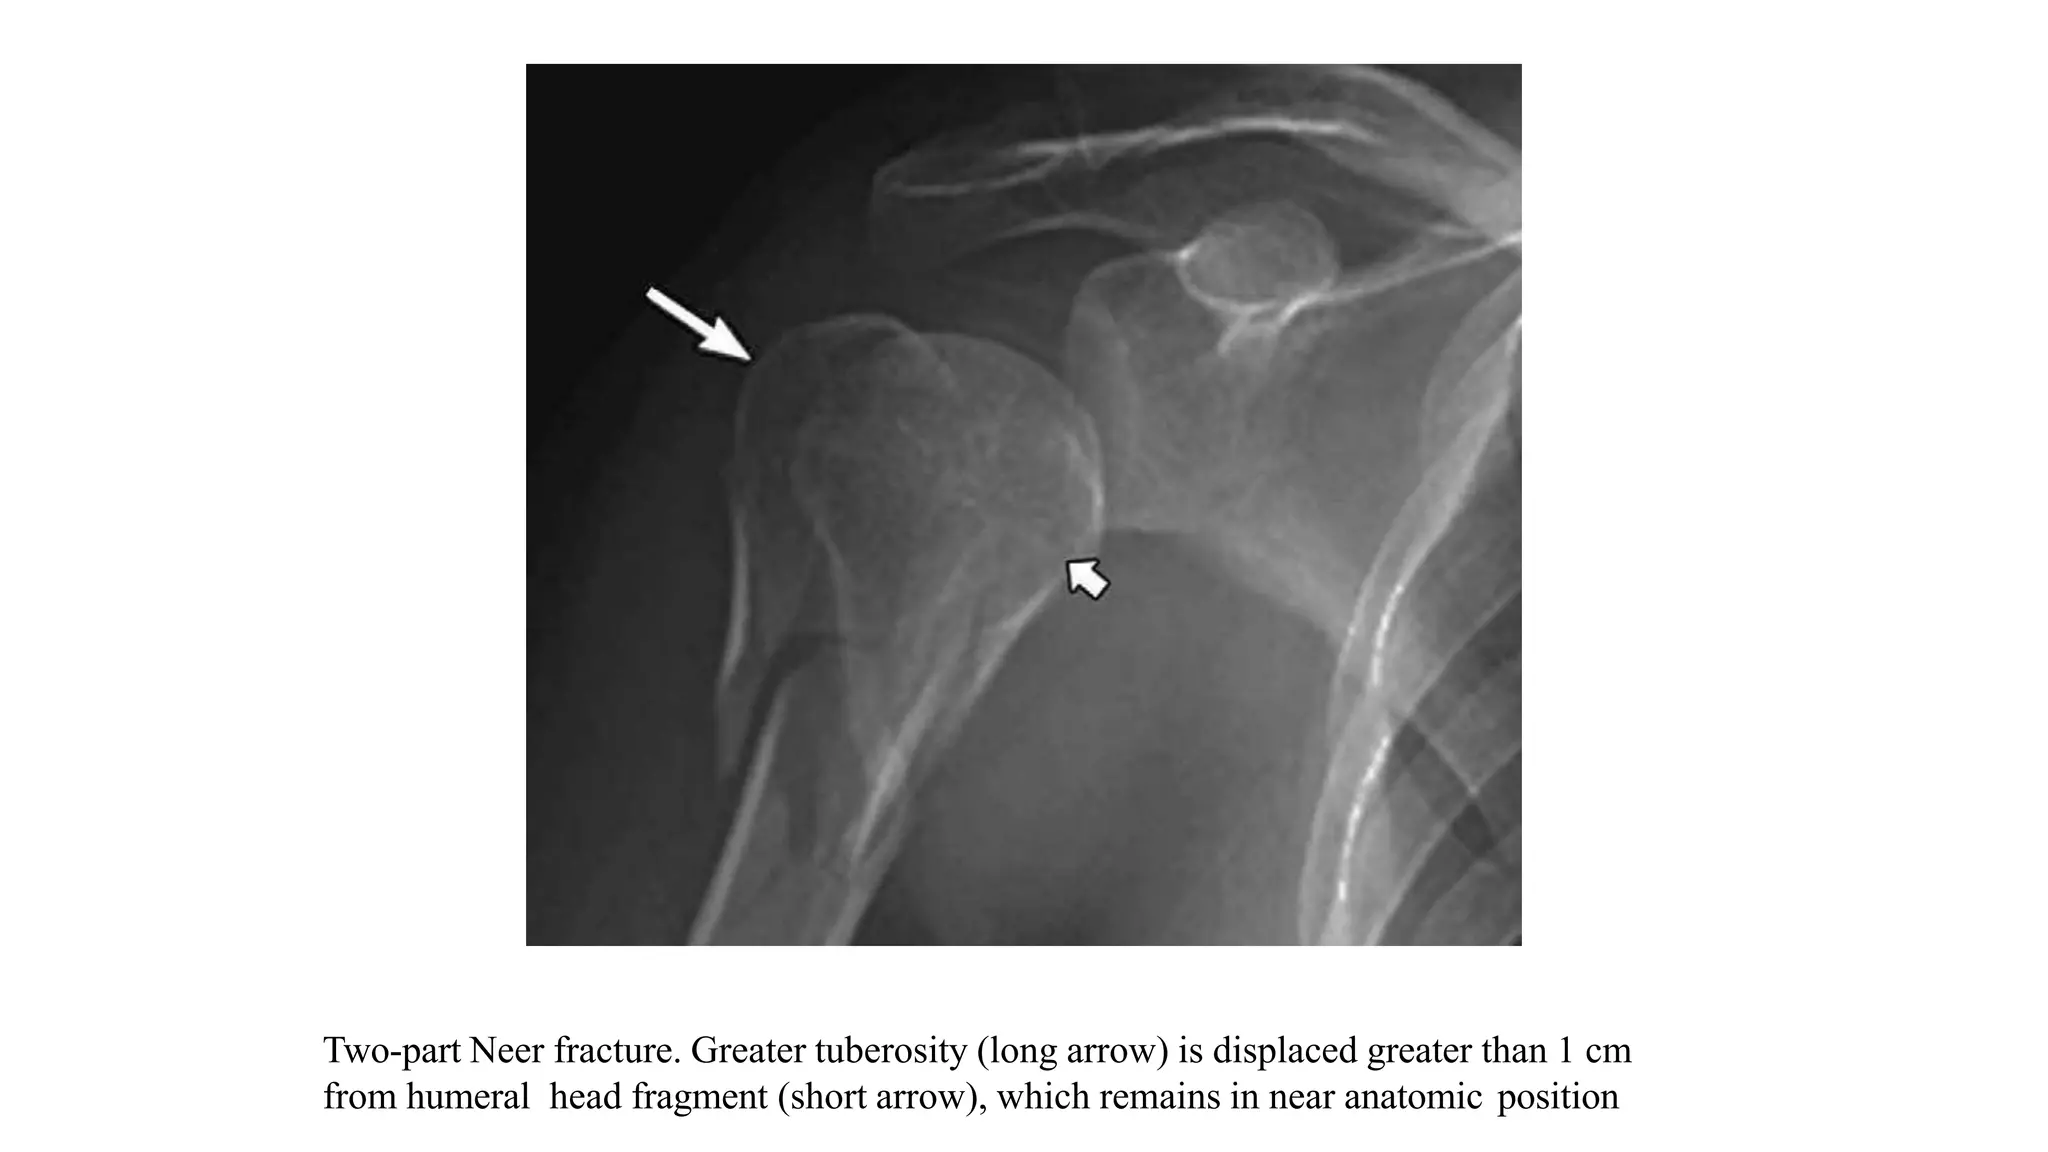

Two-part Neer fracture. Greater tuberosity (long arrow) is displaced greater than 1 cm

from humeral head fragment (short arrow), which remains in near anatomic position